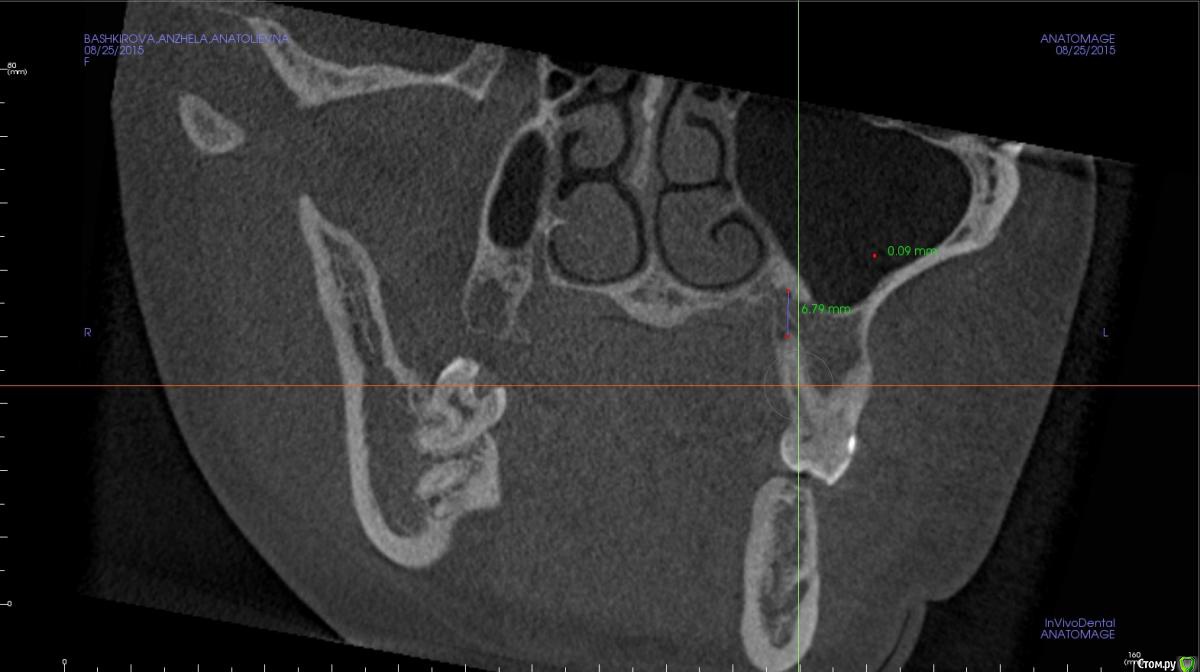

Rustam161 Опубликовано 26 августа, 2015 Поделиться Опубликовано 26 августа, 2015 Здравствуйте доктора.Необходимо произвести интрузию 26 и 27 зубов,но при осморте расположения щечных корней 26 зуба обнаружил их вестибулярное положение на снимке.В таком случае можно проводить интрузию или необходимо находить какое-то иное решение ?? Ссылка на комментарий

Yana guapa Опубликовано 26 августа, 2015 Поделиться Опубликовано 26 августа, 2015 а почему вообще все такое перекошенное? такой человек?? )) чем Вам этот корень мешает? Вы же будете МИ вкручивать между зубами. Проводите интрузию. или Вас беспокоит, что корни оголятся, так как там мало кости?? Скиньте внутриротовые фото Ссылка на комментарий

azerty Опубликовано 19 января, 2017 Поделиться Опубликовано 19 января, 2017 Что бы не плодить темы, подскажите коллеги,возможна ли интрузия моляров на верхней челюсти при очень близком расположении корней рядом с гайморовой пазухой?Не произойдет ли перфорация дна пазухи?Снимки прикреплю завтра,спасибо! Ссылка на комментарий

Opdihatop Опубликовано 22 января, 2017 Поделиться Опубликовано 22 января, 2017 Перфорации не будет скорее всего (особенно, если силы давать небольшие), но и интрузия идти будет очень медленно. Ссылка на комментарий

orthophil Опубликовано 6 февраля, 2017 Поделиться Опубликовано 6 февраля, 2017 Господа! О какой перфорации вообще идет речь. Моляры же не молотком вколачивать придется. А вот расстояние между верхушками и гайморовой пазухой уменьшится. Ссылка на комментарий